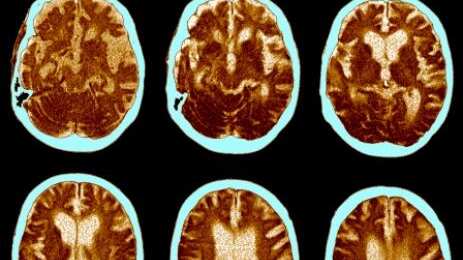

Una reciente investigación científica descubrió puntos relevantes para comprender el proceso del Alzheimer en el cerebro. Esta enfermedad es la perdida progresiva de la memoria, es la forma más común de demencia a nivel mundial y hasta ahora la evidencia médica no era suficiente para reconocer su funcionamiento precisamente.

El grupo de investigadores de la Universidad de Cambridge halló pruebas de que el Alzheimer no empieza en un punto fijo del cerebro para expandirse y matar células, sino que comienza en varias regiones del órgano. A través de la producción de grupos de proteína tóxica, mata las células, lo que produce el deterioro cognitivo, según los resultados de la investigación.

Esta y otra más, la beta-amiloide, son proteínas clave que se atascan en agregados, producen la muerte de las células y que el cerebro se encoja. Así se produce la perdida de memoria, dificultas para realizar actividades diarias e incluso cambios en la personalidad. La escala en la que se mide el grado de Alzheimer es denominada “Escala Braak”.